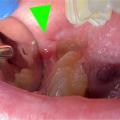

Péricoronarite

La péricoronarite (fig. 3) correspond à un accident d’éruption de la troisième molaire (dent de sagesse), survenant essentiellement chez le jeune adulte. La gencive forme un capuchon inflammatoire et douloureux venant recouvrir la dent, avec parfois un écoulement purulent à la pression.

Les douleurs surviennent notamment à l’ouverture de la bouche. Un trismus peut être associé.